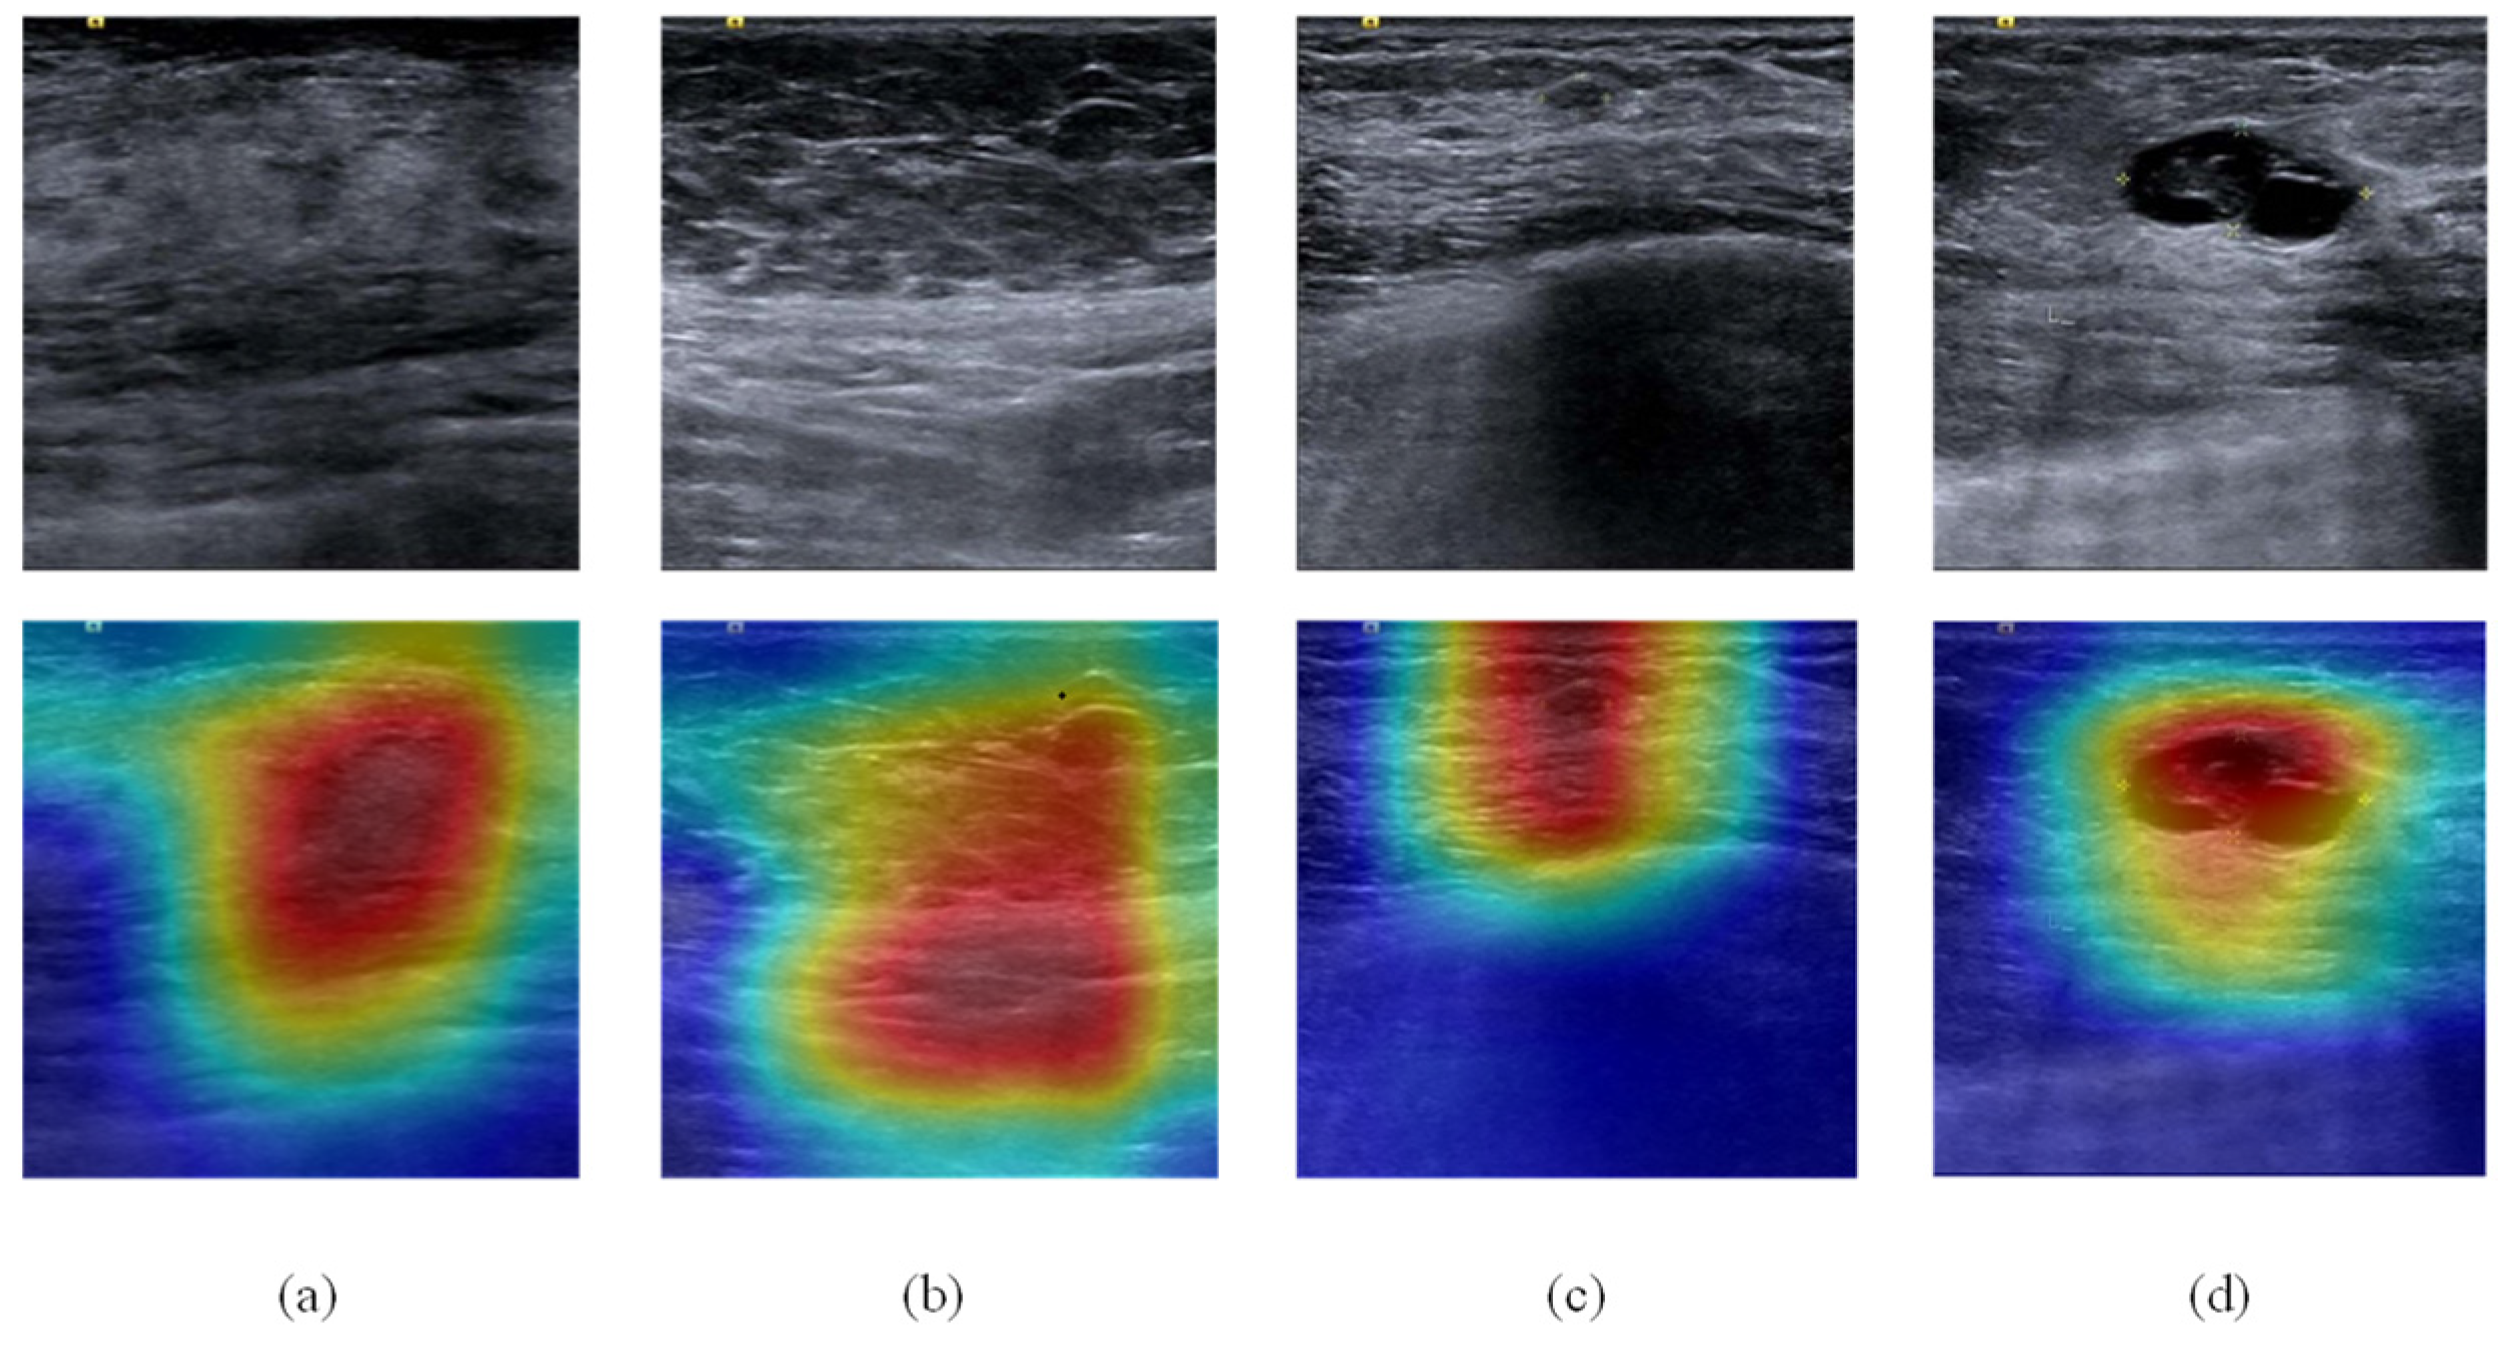

| Negative | Image | ![]() | ![]() | ![]() | ![]() |

| Number | 98 | 112 | 345 | 289 | |

| Positive | Image | ![]() | ![]() | ![]() | ![]() |

| Number | 47 | 49 | 161 | 184 | |